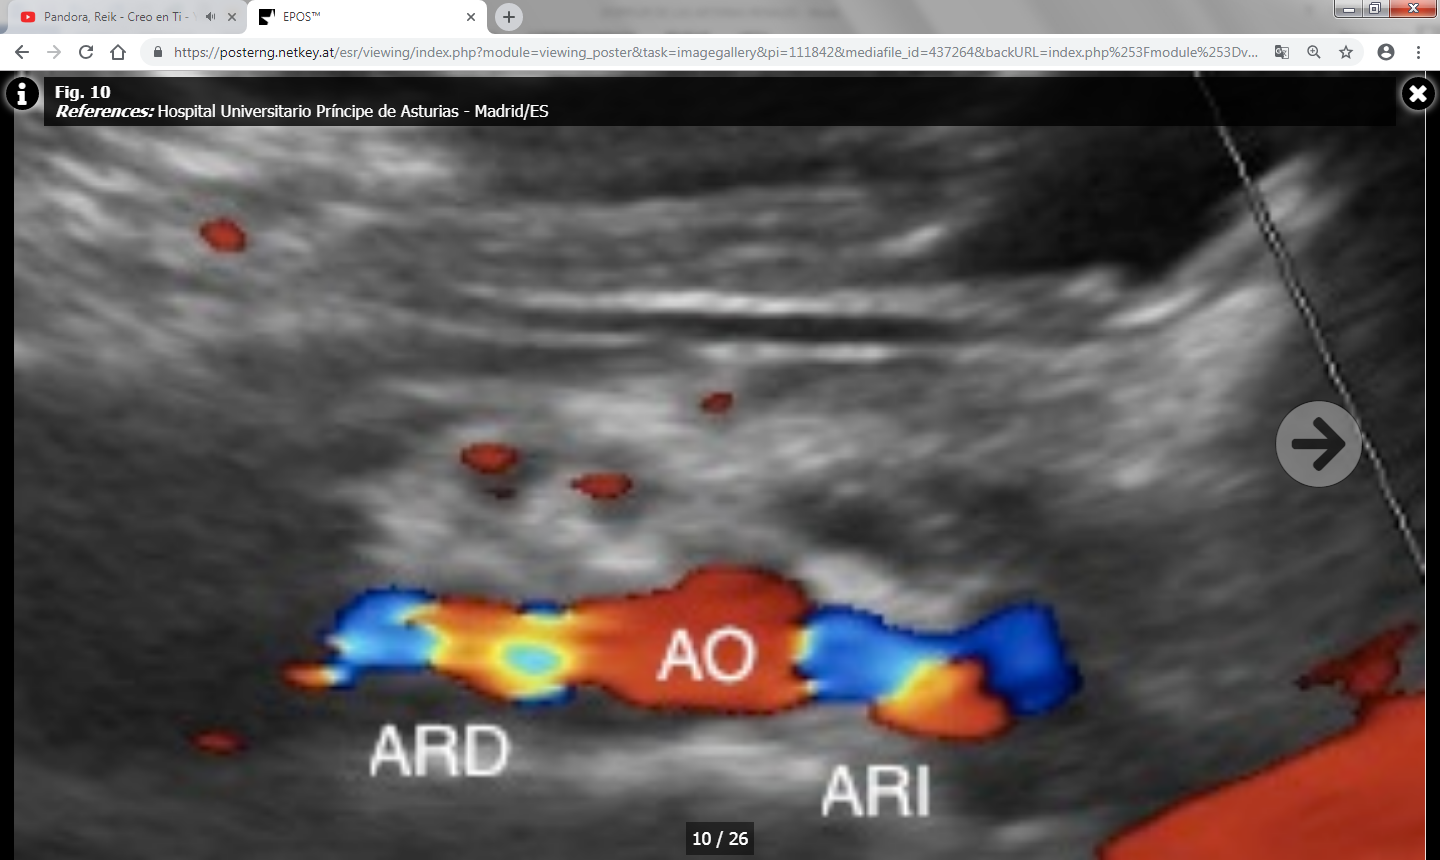

Hay dos grupos de parámetros: Directos o indirectos según se valoren en las arterias renales principales o ramas intrarrenales respectivamente.

Los parámetros directos son más fiables y reproducibles que los indirectos, y son los siguientes:

- Índice reno-aórtico (cociente entre la VPS de la arteria renal y la aorta): Normal por debajo de 3.5-3.6.